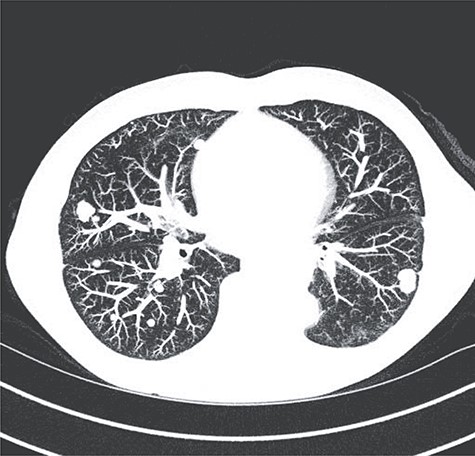

Imaging revealed tumor dimensions of 15–18 cm in diameter (Fig. 1). Following endoscopic ultrasound and positron emission tomography scan, a multidisciplinary board recommended surgical resection with esophagectomy through a thoracoabdominal incision. He was placed in a semirecumbent position. The costal margin was divided. The diaphragm was divided in a circumferential fashion leaving a rim of diaphragm on the chest wall. Gastric preparation was performed first (Fig. 2). Then, dissection was carried out along the mass into the chest. The mass was adherent to the pericardium and aorta but was encapsulated and not invading those structures. Multiple large aortoesophageal vessels were divided with the Ligasure vessel sealer device (Medtronic MN, etc.). The left lower lobe and inferior pulmonary vein were splayed across the mass. Inadvertent injury of a branch of the inferior pulmonary vein required vascular repair. The mass emanated from the lower one-third of the esophagus (Fig. 3). The esophagus was divided at the level of the left inferior pulmonary vein and the mass removed. Frozen sections of the esophagus, surrounding pleural, pericardium and lung, were performed and were negative. The anastomosis was performed in a typical fashion with a circular end-to-end stapler. The diaphragm was reapproximated, and the extra conduit length was tacked down into the abdomen. The immediate postoperative course was largely uneventful, with negative radiographic leak test performed on postoperative Day 5 and the patient discharged to home on postoperative Day 7.

Axial image from preoperative CT of the chest demonstrating extension from esophagus and relation to the pericardium and thoracic aorta.

Surveillance scans were negative until 9 months later when multiple bilateral pulmonary nodules were discovered (Fig. 6). Biopsy of one of the nodules revealed recurrent, metastatic disease. He was treated with pembrolizumab for three cycles but had progression. He was then switched to gemcitabine and docetaxel for three cycles but had progression. Most recently, he underwent six cycles of doxorubicin, which showed stable disease.